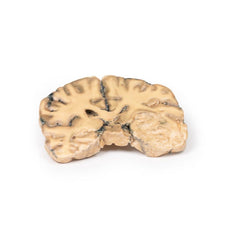

3D Printed Astrocytoma

Clinical History

A 73-year-old female was admitted with new left-sided hemiplegia. On further questioning she

revealed a 3-month history of headaches, nausea and deteriorating balance. CT brain revealed an inoperable brain

tumour. She died 1 week after being admitted.

Pathology

This brain specimen is a coronal section. In the right temporal lobe, a poorly demarcated tumour is

present. There is enlargement of the hemispheres and flattening of the gyral pattern. From the posterior aspect

of the specimen subfalcine herniation* is appreciated and the tumour appear less well differentiated with

haemorrhagic and necrotic foci. Histology of this tumour showed an astrocytoma, Grade III/IV.

*In subfalcine

(or cingulate) herniation, the most common type of brain herniation, the innermost part of the frontal lobe is

pushed under part of the falx cerebri, between the two hemispheres of the brain.